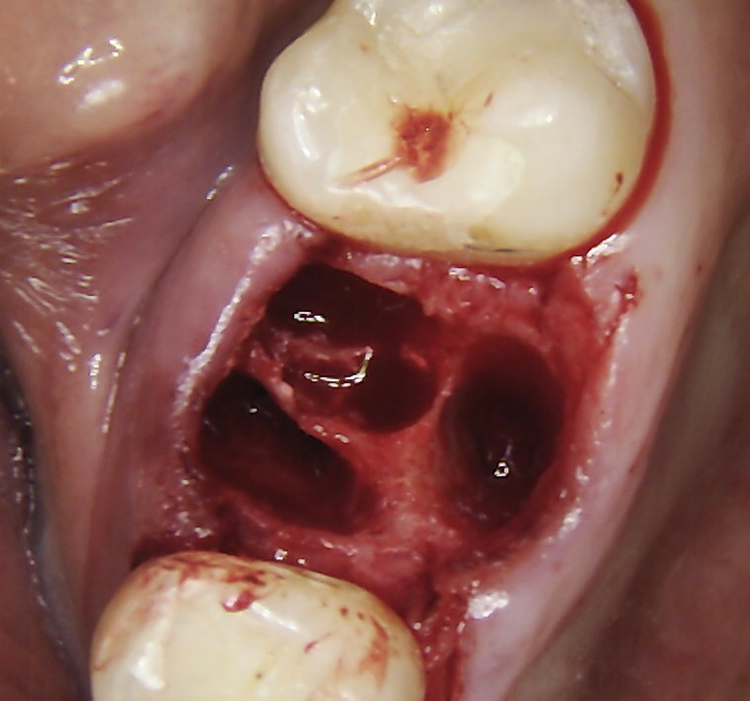

Abb. 4: Repräsentativer Fall von Grad A Typ III. a) Ansichten vor der Implantation. Röntgenbild der periapikalen Läsion an einem wurzelkanalbehandelten Molaren. b) Die Extraktionsalveole zeigt ein interradikuläres Septum vom Typ III (B).

Bei dem balkonförmigen Implantat blieben die Alveolarkämme und der Kronenansatz erhalten (Abb. 4c und d). Der Spalt zwischen dem Implantat und der bukkalen Lamelle wurde mit A-PRF und einem Kollagenblock aufgefüllt, so dass keine zusätzliche Knochenaugmentation erforderlich war. Zusätzlich wurden PRF-Matrizen um, über, unter und neben dem Implantat im Knochen-Implantat-Raum positioniert (Abb. 1 bis 4b). Außerdem kam eine optionale Einheilscheibe (6 x 8 mm) zum Einsatz, um das Kollagen und die PRF zu sichern (Abb. 3b). Die Implantate zeigten bei einem Drehmoment von 35 Ncm Stabilität, welche mit dem Periotest-Gerät von Medizintechnik Gulden getestet wurde. Die Werte des Implantatstabilitätstests, die im Bereich von –8 bis 0 lagen, wurden als ideal für die Belastung angesehen (Tab. 3).

Die Implantate wurden mit einer minimalinvasiven Technik ohne vertikale Entlastungsschnitte unter Lokalanästhesie (Articain 40 mg/ml mit Epinephrin 10 µg/ml; Sanofi) und von dem gleichen Chirurgen gesetzt. Eine gründliche Inspektion und Kürettage der Operationsstellen wurden durchgeführt. Advanced Platelet-Rich-Fibrin (A-PRF und i-PRF), hergestellt mit dem Low-Speed-Zentrifugationskonzept (Mectron), wurde an der Eingriffsstelle über und um das Implantat herum platziert [8]. In das Vestibül der Eingriffsstelle und zur Befeuchtung des Kollagenblocks wurde i-PRF injiziert.

Die Augmentation des Alveolarkamms richtete sich nach der Größe des Defekts. Der Kollagenblock (Condress 5 x 5 cm, Smith & Nephew) wurde auf die erforderliche Größe zugeschnitten und am Alveolarkamm sowie um das Implantat herum verdichtet. Zur Stabilisierung der A-PRF-Matrizen und des Kollagenblocks sowie zur Repositionierung des Lappens wurde eine nicht resorbierbare monofile Naht (Atramat® 5-0, Mednaht) verwendet. Vor der prothetischen Belastung mussten die Implantate 4–8 Wochen einheilen.